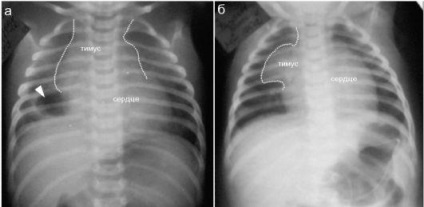

diagnózis thymomegaly

Thymomegaly fejlettségű gyermekek definíciója szerint attribútumok (megjelenés a rák röntgen), és az eredményeket a speciális méréseket.

Minőségi jellemzői diagnosztizálására fokú felbontás thymomegaly thymus árnyéka a röntgenfelvételen. A kezelési rend választjuk szigorúan egyénileg, attól függően, hogy a betegség, az általános állapot, az immunrendszer és a súlyosságát a gyermek életkora.